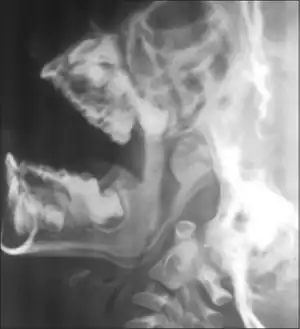

X-ray nasopharynx lateral view open mouth revealed moderate adenoid hypertrophy

4. X-ray lateral view of nasopharynx